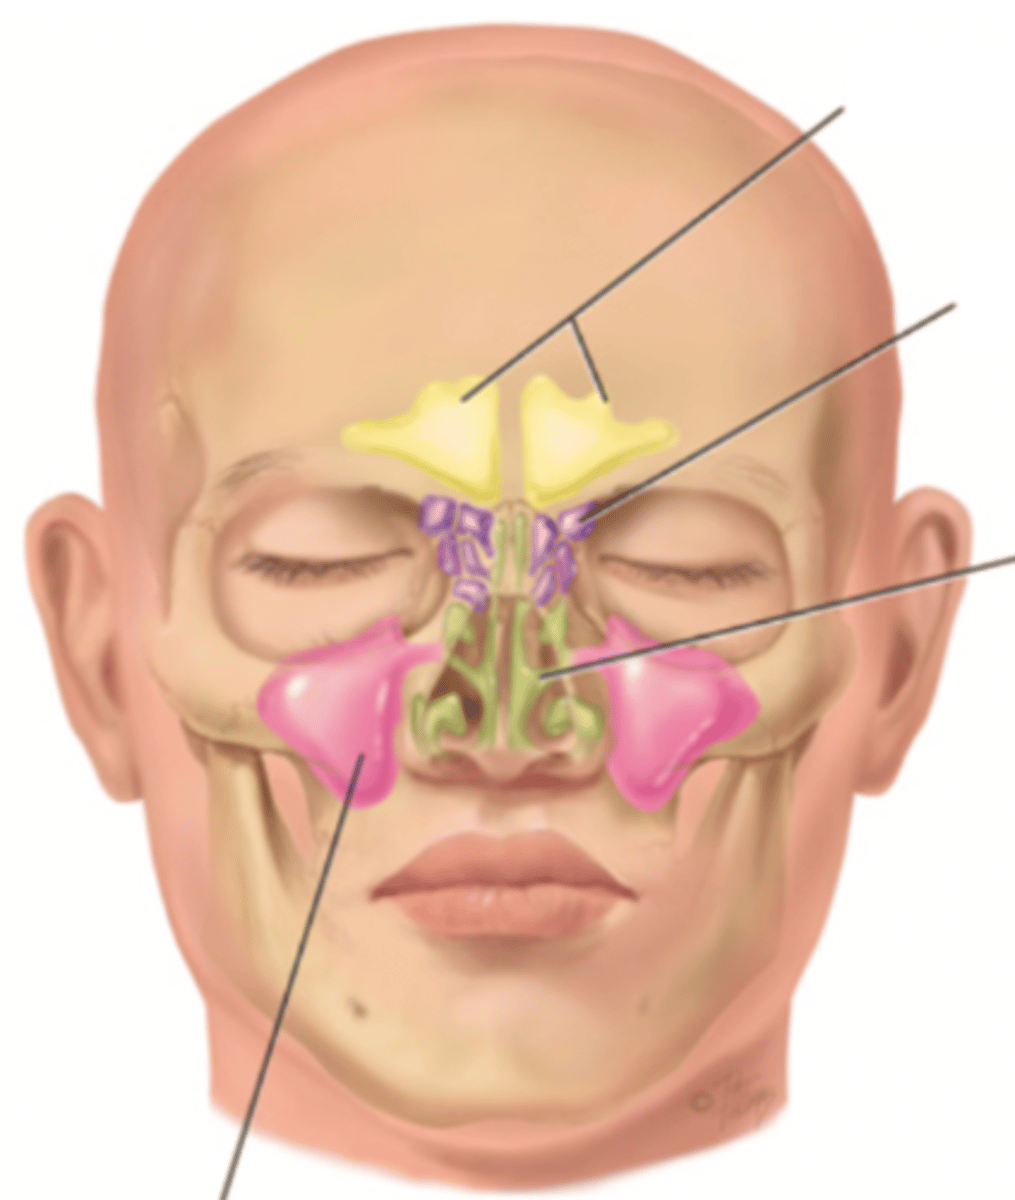

Nose

Organ of smell

Bridge

Tip

Ala

Nares

Columella

Vestibule

Nasal Cavity

Hollow space behind the nose

Turbinates (Conchae)

- Bones that protrude into the nasal cavity- that increases surface area for filtering dust and dirt particles by the mucous membrane

- There's an inferior, middle, and superior one (2.), 3.), 4.))

Olfactory Region

A dime-sized area at the top of each nasal cavity that houses sensors responsible for smell (1.))

Hard (Bony) Palate

Anterior palate portion that is supported by the palatine processes of the maxillae and the palatine bones (8.))

Meatuses

- Constricted passageways in the nasal cavity that produce air turbulence

- There's an inferior, middle, and superior one

(5.), 6.), 7.))

Soft Palate

Posterior palate portion, not supported by bone (9.))

Paranasal Sinuses

- Frontal

- Ethmoid

- Sphenoid

- Maxillary

Frontal Sinus

Cavity within the frontal bone (yellow)

Ethmoid Sinus

Mucosa lined air spaces located above the sphenoid sinus and below the frontal sinus (purple)

Sphenoid Sinus

Sinus above and behind the nose (green)

Maxillary Sinus

Sinus on either side of the nasal cavity below the eyes (pink)

Functions of the Nose